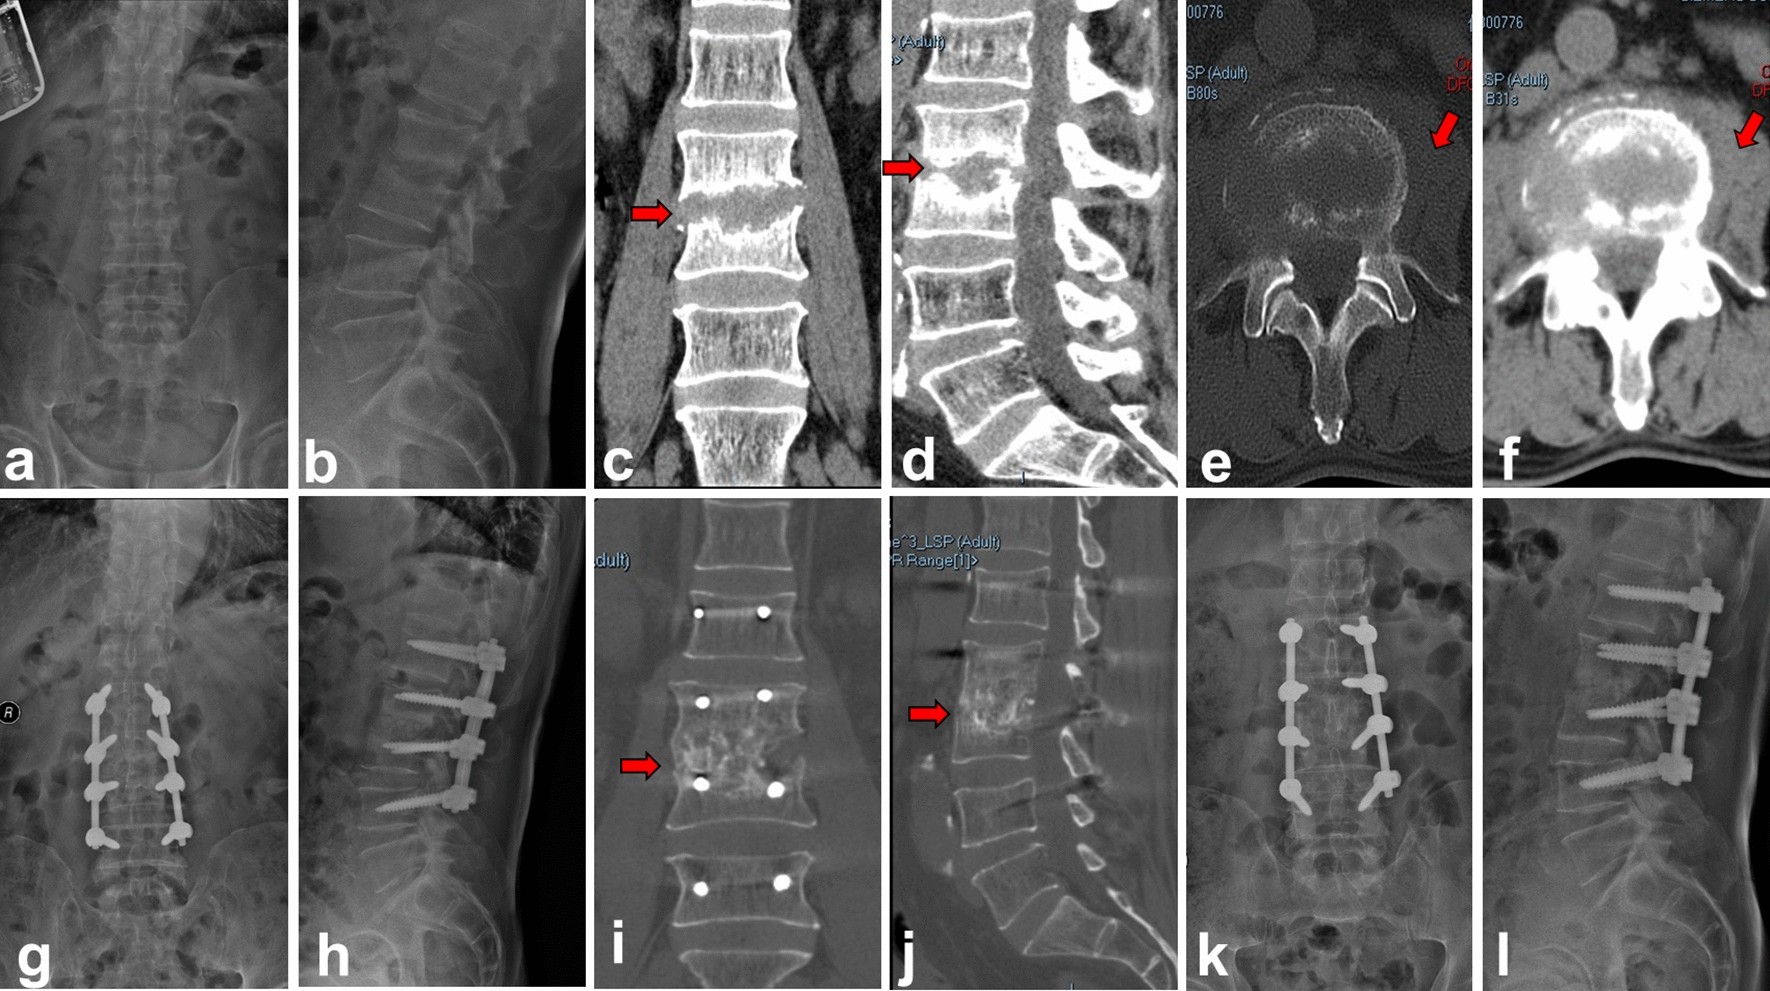

Figure 3

Autologous iliac bone group (group A). A 68-year-old male with L3–4 lumbar pyogenic spondylitis (a–f). Preoperative X-ray and CT showed that L3–4 vertebral body destruction with sequestrum formation, intervertebral space stenosis and psoas abscess (red arrow). (g,h) Postoperative X-ray showed iliac bone graft and internal fixations were in good location. (i–l) CT and X-ray taken at 6 months after operation showed solid bone fusion between L3 and L4.